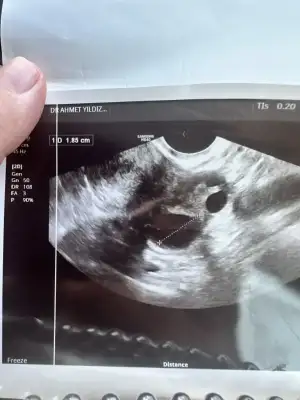

Kızlar rahim ultrason anlayan var mı yumurtan çatlamış dedi doktor ama kanda gebelik çıkmadı lütfen bilen varsa yorum yapabilir mi kızlar 🥹🥹🥹

canım 18.5 mm ölçmüş yumurta bu çatladığını nasıl anladı acaba 🫣 benim dr umda yltrasonda gördü bu ay banada muhtemelen çatlamış içi kanlanmış yumurtanın dedi

Canım bana da çatlamış görünüyor dedi kafam çok karıştı şuan ilişki olmalı mı yoksa şansım yok mu bu ay regl olur muyum sence